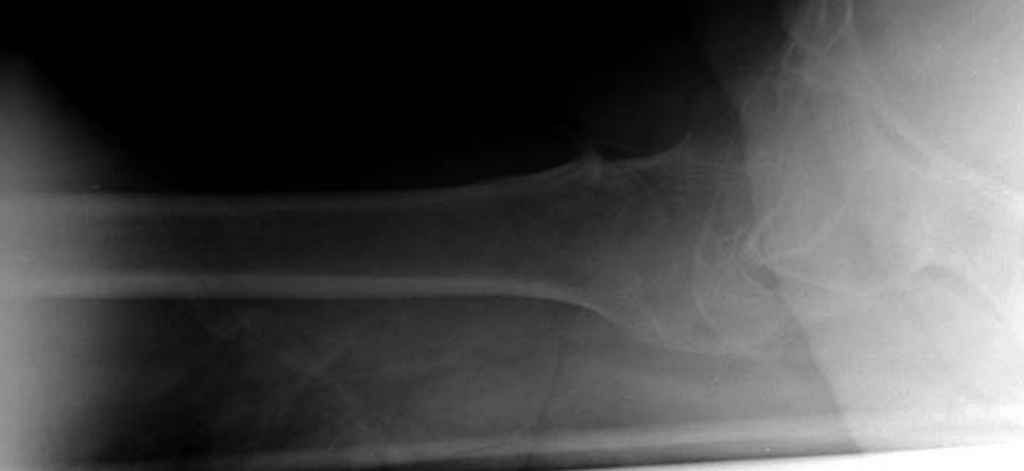

На мой взгляд, причиной телескопирования явилось несоответствие диаметра гамма нэйл с диаметром канала подвертельного отдела бедра: обратите внимание на величину протрузии шеечного винта и величину медиализации дистального фрагмента - они одинаковы, смещение или телескопирование фрагментов происходило до того момента, пока гамма нэйл не упёрся в медиальный кортекс и образовалось пространство между латеральным

кортексом и латеральной поверхностью гвоздя.